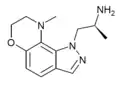

5-MeO-MPMI | 5-Methoxy-3-{[(2R)-1-methylpyrrolidin-2-yl]methyl}-1H-indole | 143321-57-7 |

|